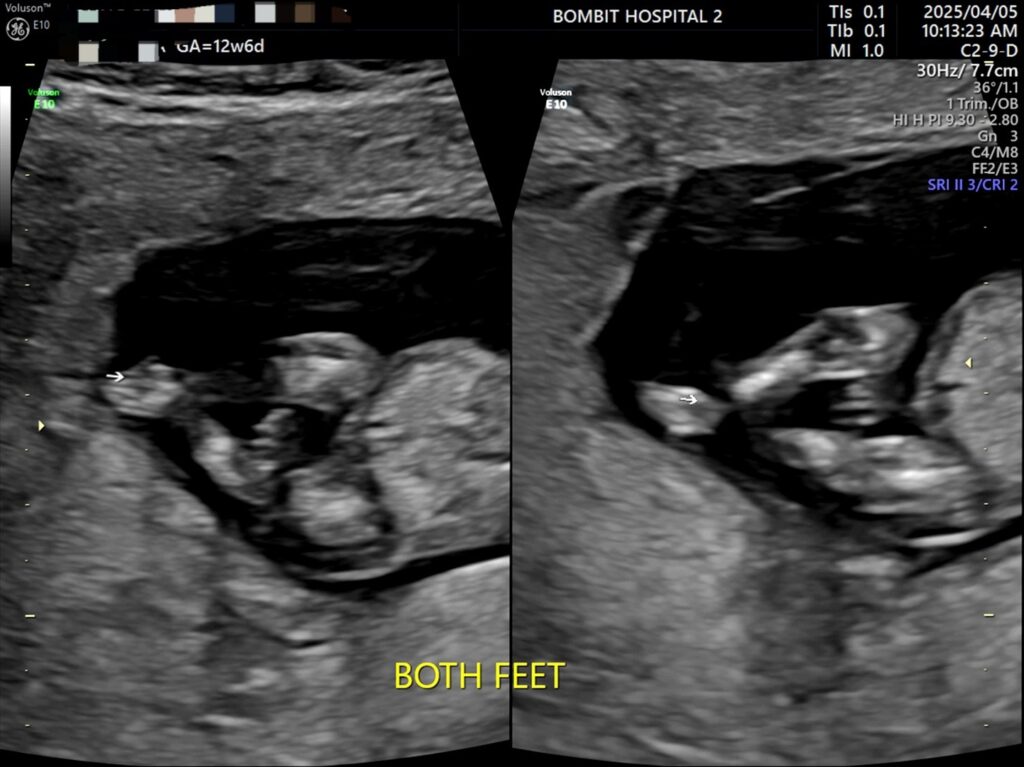

봄빛병원에 다시 방문. 정밀초음파도 하고, 다시 진료도 보았다.

피고임은 이제 없어졌다고 했다. 약간은 느려진 듯한 심장소리도 다시 들었고 니프티 검사용 채혈도 했다.

정밀초음파 사진.